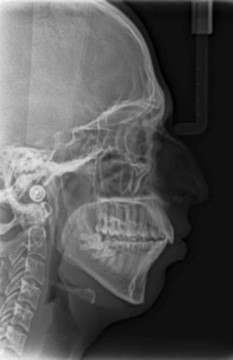

Post treatment lateral cephalometric radiograph was taken to assess the treatment changes. (Figure 9). The changes in maxilla in the anteroposterior direction was insignificant, however an increase in the length of the mandible measured from Condylion (Co) to Gnathion (Gn) and an increase in anterior facial height was observed. Maxillary incisors were retracted dramatically by 8mm and the mandibular incisors were proclined by 3mm to camouflage the skeletal class II malocclusion.(Table 1). Effective expansion of the maxillary constriction as an end-of treatment goal was achieved. (Figure 10a,Figure 10b).

Figure 9.Post-treatment lateral cephalometric radiograph

| Variable | Norm | Pre-treatment | Post-treatment |

| SNA (degrees) | 82 ± 2 | 80 | 80 |

| SNB (degrees) | 80 ± 2 | 72.5 | 71 |

| ANB | 2 ± 2 | 7.5 | 9 |

| U1 to NA (degrees) | 22 | 26 | 17 |

| U1 to NA (mm) | 4 | 9 | 1 |

| L1 to NB (degrees) | 25 | 30 | 33 |

| L1 to NB (mm) | 4 | 8 | 11 |

| N-Me (mm) | 123 ± 5 | 112 | 142 |

| N-ANS (mm) | 56 ± 3 | 53 | 66 |

| ANS-Me (mm) | 70 ± 3 | 59 | 78 |

| FMA (degrees) | 25 | 32 | 36 |

| Co-Gn (mm) | - | 102 | 121 |

| E-plane LL (mm) | -2 ± 2 | 2.5 | 5 |